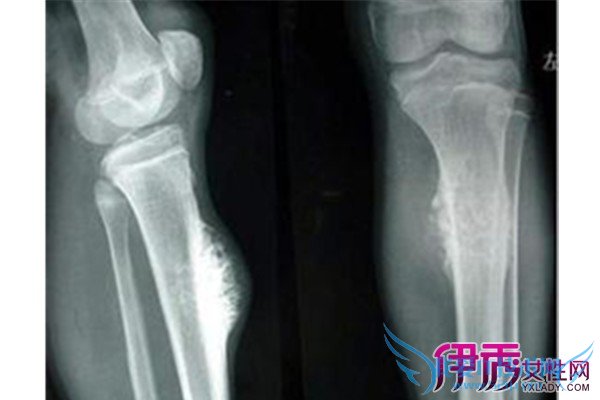

4)畸形 由于肿瘤的存在,可引致发育不对称,或压及骺板,可引发畸形。

6)病理骨折 由于肿瘤存在及其破坏作用,易致病理骨折。如巨细胞瘤每无症状,常在发生病理骨折才被发现。

(3)畸形 由于生长年龄、部位、肿瘤性质等因素,可引发畸形。如多发性软骨瘤,影响生长,可质肢体弯曲、不等长。内生软骨瘤因膨胀可使手足小骨畸形。肿瘤侵及骺板亦可引起发育异常。